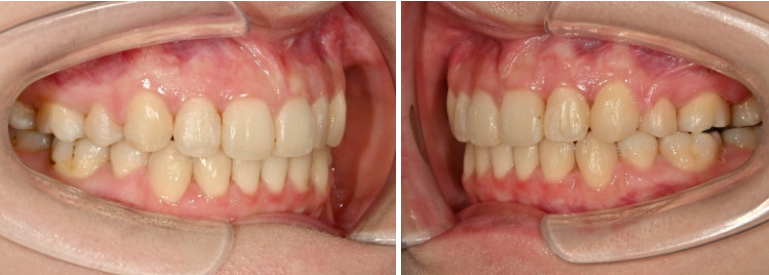

23년 7월 교정치료를 위해 내원한 20대 환자분입니다.

오래 전 비발치교정을 했던 이력이 있습니다.

앞니는 가지런한 편이며 중심선도 거의 맞습니다.

교합은 좋은 상태이고

치열도 꽤 가지러한 편입니다.

입안 사진만 보면 재교정을 왜하나 싶겠지만 환자분이 재교정을 해서라도 고치고 싶은 것은

돌출입

거미스마일 입니다.